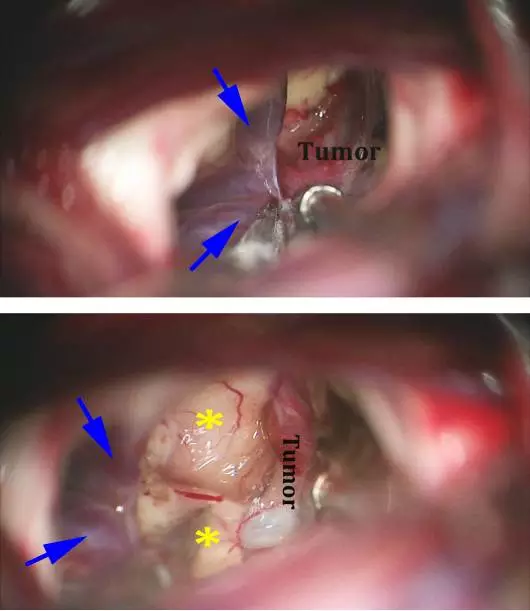

图12. 采用显微剪刀分离双侧大脑内静脉(蓝色箭头)后显露肿瘤包膜后方(上图)。这一分离有助于识别三脑室壁(*)和囊肿后壁(下图)。